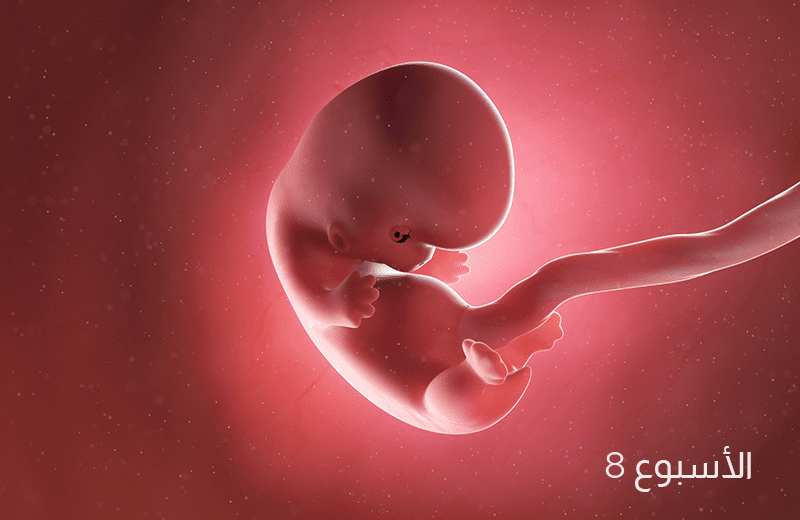

في الأسبوع الثامن من الحمل، ينمو طفلك بمعدل ملليمتر واحد في اليوم وتتشكل الشفاه والأنف والجفون، وعلى الرغم من أن الحمل قد لا يكون ظاهراً عليكِ، إلا أنك قد تلاحظين أن ملابسك أصبحت ضيقة بعض الشي.

طفلك الآن بحجم حبة الفاصوليا، يبلغ طوله 14 مم تقريباً، ويزن حوالي 2غم.

تستمرّ الأطراف بالاستطالة وتتكون الأصابع، ويتراوح طول الجنين في هذا الأسبوع ما بين 11-14 ملم، تتّضح وتظهر عيونه، وتتشكّل الشفة العليا والأنف، ويبدأ ظهره ورقبته بالاستقامة تدريجيّاً.

قلبُ طفلك ينبضُ الآن بمعدل (150- 170) نبض في الدقيقة، أي ما يعادل ضعف معدّل نبضات قلبكِ.

تطورٌ آخر جديد هذا الأسبوع، طفلكِ يقوم بحركات عفوية من الممكن أن تشعري بها.

يبدأ الجنين بالتحرك ابتداء من الأسبوع الثامن من الحمل، ولكن حركاته قد لا تشعرين بها وخاصة إذا كان هذا حملك الأول، ويتم الكشف عنها فقط بالتصوير بالموجات فوق الصوتية.